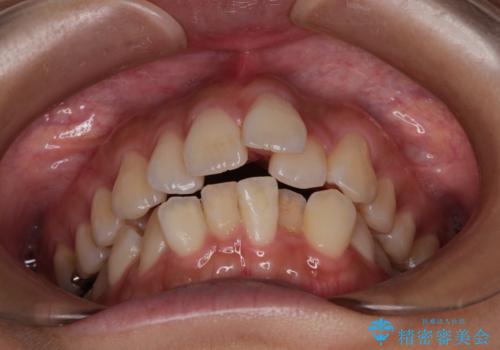

- 上下の出っ歯を気にして来院された患者様です。

口元を積極的に引っ込めるために、上下左右の第一小臼歯を4本抜歯することとしました。